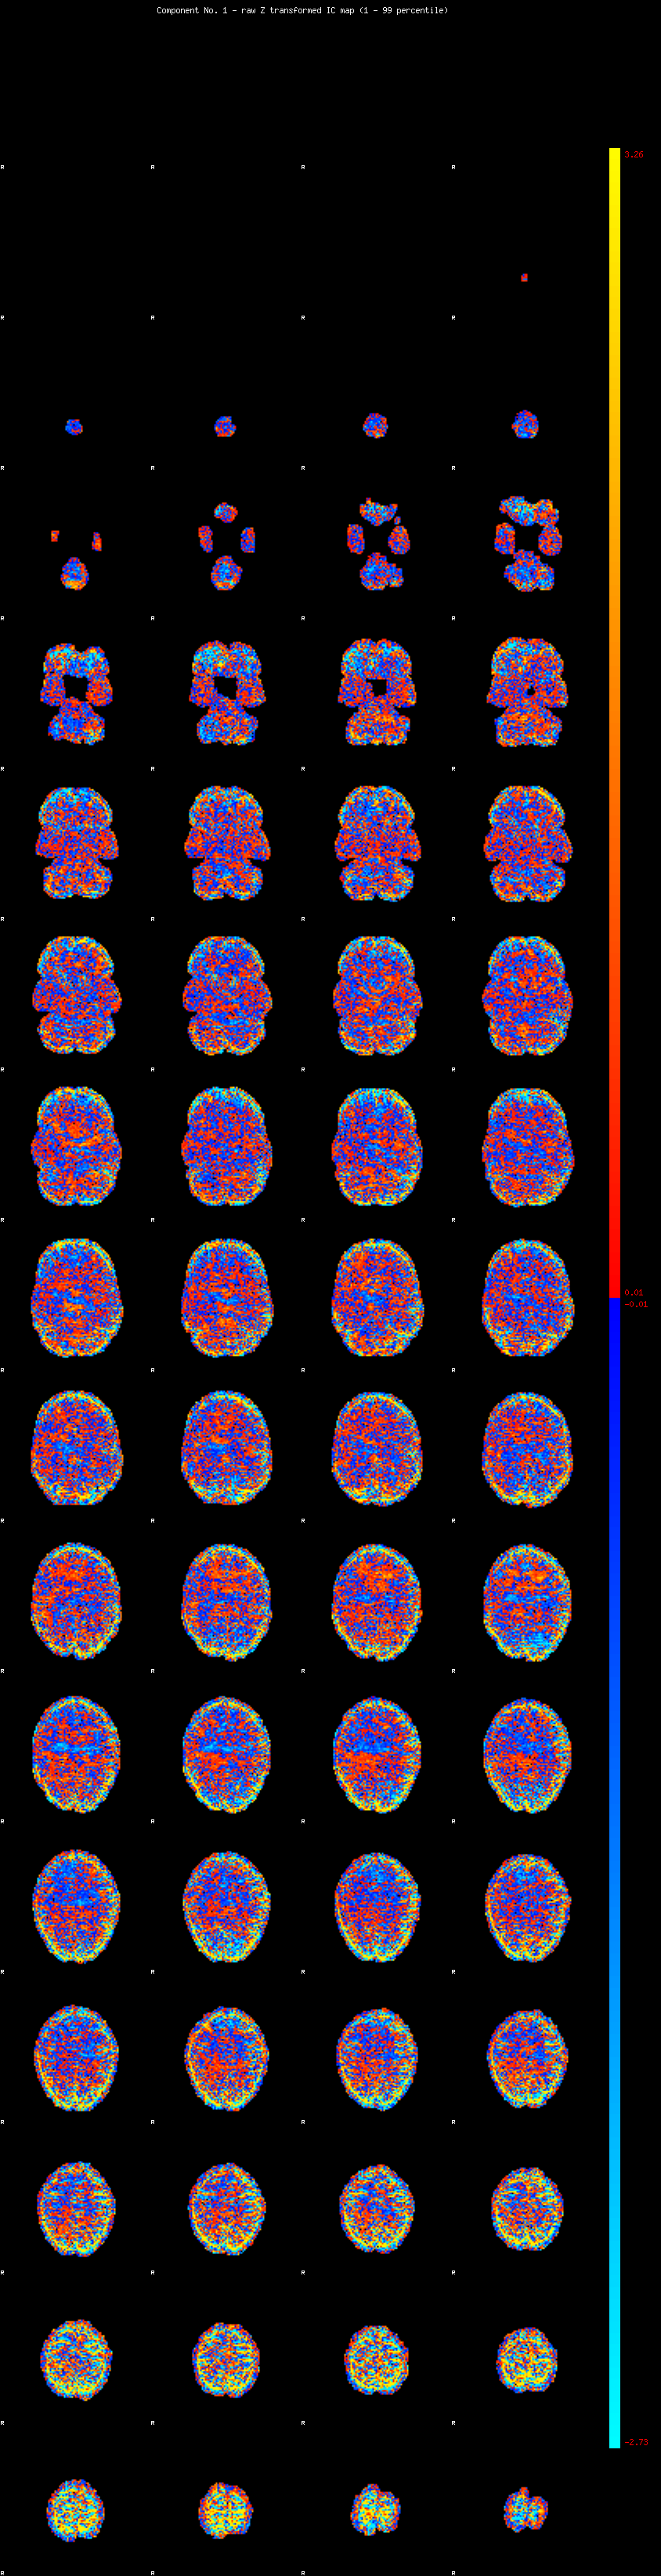

IC_1 Mixture Model fit

Means : -0.000000 3.499355 -2.888690

Vars : 1.000000 5.800963 3.292438

Prop. : 0.815749 0.099092 0.085159